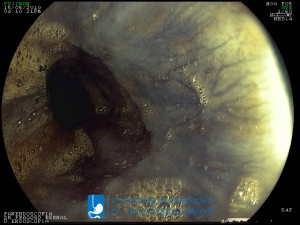

La Unidad de Endoscopía fue creada en 2002 por el Dr. Jesús Fragoso Bernal, es pionera en el estado por la utilización de la tecnología más avanzada, que nos permite ofrecer servicios integrales de diagnóstico y tratamiento para las enfermedades del aparato digestivo.